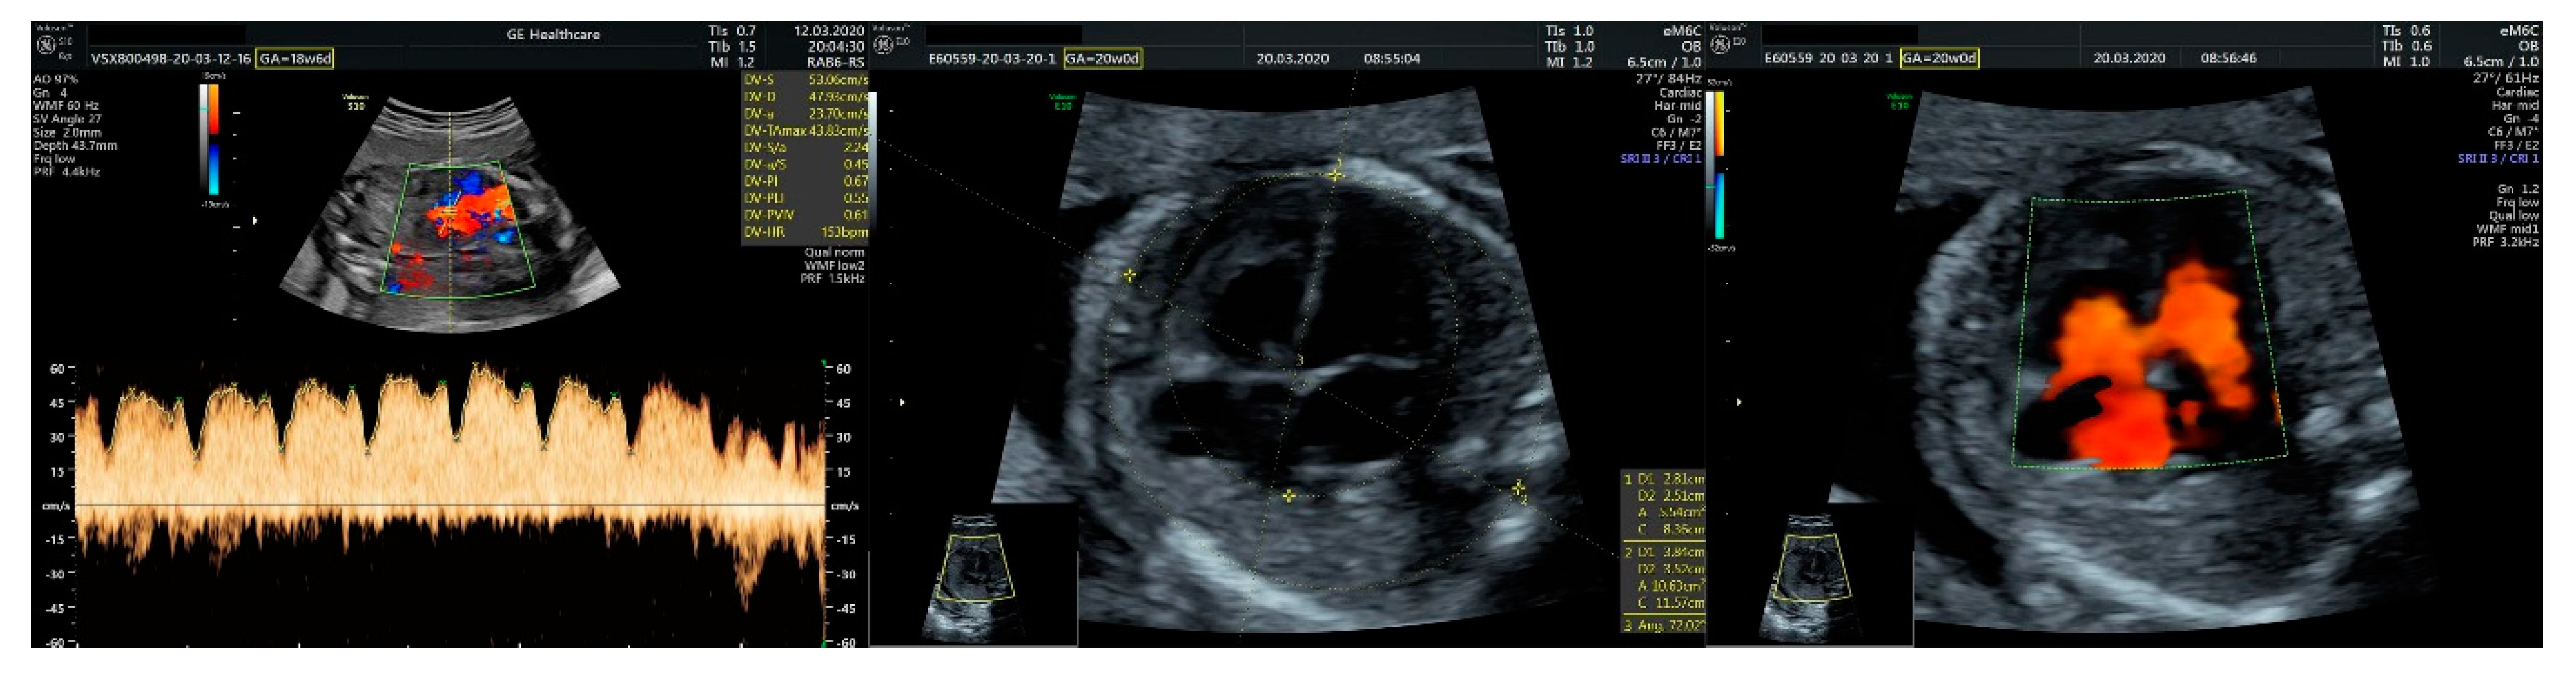

2.1. Ultrasound Findings

- an isolated aortic arch anomaly (supposedly aneurysmal dilation from which the left common carotid artery emerges) and coarctation of the aorta with the anterograde flow;

- ventricular septal defect, coarctation of the aorta, and a vascular formation located superior from the aortic arch with the appearance of an arteriovenous fistula;

- aneurysmal dilation located above the pulmonary trunk bifurcation and a dilated left common carotid artery with a retrograde flow;

- minor ventricular septal defect with a normal ductus venosus triphasic flow.